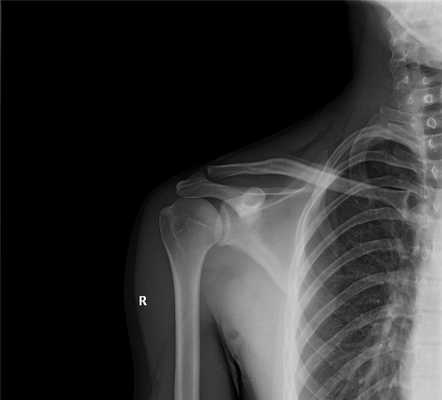

Если все вышеописанные приёмы не позволяют врачу полностью оценить картину заболевания, обычно переходят к следующей стадии диагностики — рентгену.

Рентген представляет собой способ рассмотрения внутреннего строения костей плечевого сустава пациента с помощью лучей определённого диапазона.

Рентген в двух проекциях (прямой и осевой) довольно чётко может показать отклонение текущего состояния плечевого сустава от нормы. На снимках можно увидеть, насколько смещена головка плечевой кости, каково направление её смещения, а также наличие переломов костей (если они есть). С помощью рентгена можно определить тип вывиха и предположить развитие возможных осложнений. Не допускается вправлять вывих без предварительного проведения рентгена.

Проведя рентгенографию костей плеча, можно обнаружить подвывих. Это состояние схожее с вывихом, но контакт между поверхностями лопаточной и плечевой кости утрачивается не полностью, а частично.

Все кости на рентгене отображаются в виде плотных белых образований. Переломы костей, а также трещины на них выглядят на снимках как тёмные полосы, расположенные в различных направлениях и имеющие различную локализацию и размер. Фото-рентген плечевого сустава позволяет обнаружить наличие переломов плечевой кости, ключицы и лопатки. Снимок нужен для того, чтобы определить сложность перелома, увидеть, как расположены осколки костей (если имеет место раздробление).

Сближение костей плечевого сустава — это первое, что показывает рентген. Межсуставная щель сужается вследствие истирания хрящей, а значит в дальнейшем при активных движениях процесс истирания будет переходить уже непосредственно на костную ткань.